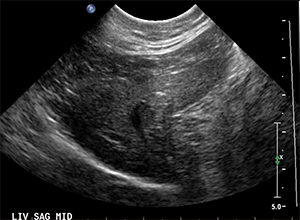

Abdominal ultrasound shows both kidneys are enlarged with irregular margins and perirenal hypoechoic rims. Both renal cortices are also mottled in appearance with ill-defined multiple hypoechoic nodules. A small amount of aggregation of gravity-dependent hyperechoic sediment is present within the urinary bladder (not pictured).

Image of right kidney: